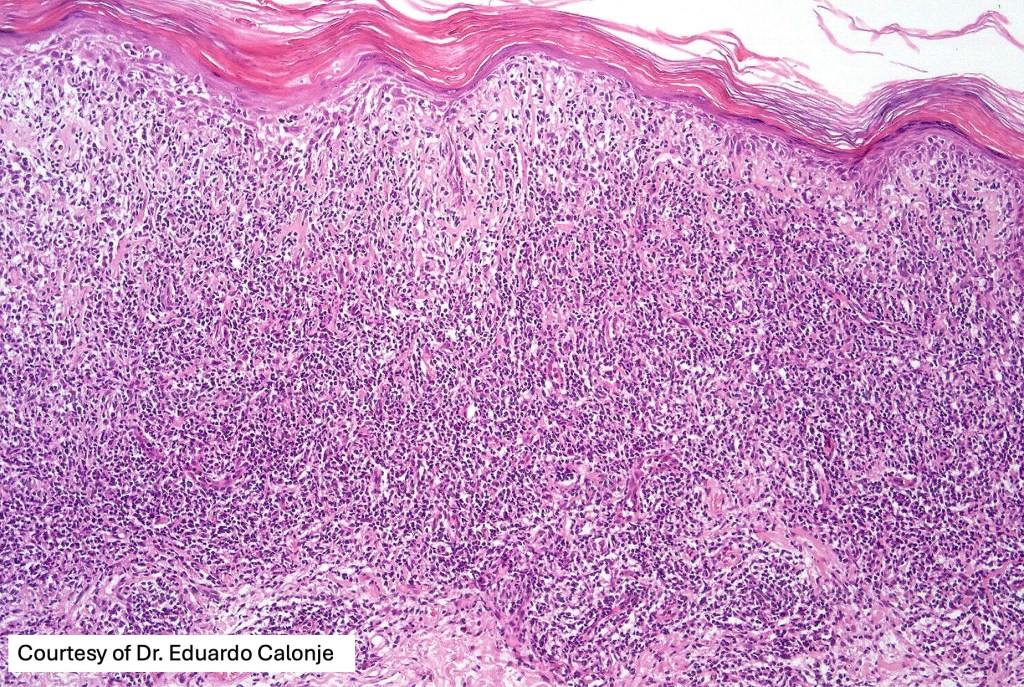

Histological features

The histological hallmark of mycosis fungoides is the presence of large atypical lymphocytes with a convoluted/cerebriform nuclear border (Sézary cells). These may be found at the epidermal-dermal jnuction and as collections within the epidermis (Pautrier microabscess). These are most easily found in plaque stage disease. The epidermal component can be subtle in patch stage disease and is often lost in tumor stage dsease. The classification into patch, plaque & tumor stage disease is less helpful histologically as the features merge from one to the other. It is all a matter of degree.

Patch stage disease

•Changes can be subtle & dependent on clinicopathological correlation; in many patients sequential biopsies over many months may be necessary to establish the diagnosis.

•Mild hyperkeratosis & focal parakeratosis, acanthosis, epidermal atrophy or of normal thickness

•Superficial dermal lymphocytic infiltrate containing variable numbers of Sézary cells with atypical, irregular, hyperchromatic nuclei surrounded by a halo; these can be very few in number and dependant on viewing multiple levels

•Palisading of atypical lymphocytes along the epidermal-dermal border

•Pautrier microabscesses may be present but are often absent in patch stage disease

•Variable interface change with keratinocyte necrosis & pigmentary incontinence

•Eosinophils & plasma cells sometimes present

•Coarse collagen bundles in the papillary dermis can be a feature but this is not as marked as seen in plaque disease

.Although in typical mycosis fungoides fungoides, spongiosis is absent, exceptionally it can be a feature